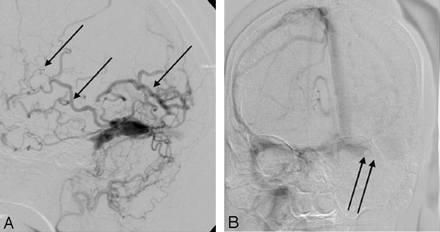

The imaging studies included noncontrast CT scan, 3D time-of-flight MR angiography (MRA) and MR imaging. CT demonstrated subcortical calcification, cerebral sulcus effacement, and a low attenuation area in the subcortical white matter on the left side (Fig 1). MR imaging (Fig 2) revealed multiple enhanced, punctate, and linear signal intensity voids, which indicates the presence of vessels over left cerebrum, and MRA showed multiple abnormal engorged vessels, which arose mainly from the external carotid artery. The left-side transverse sinus and sigmoid sinus were not identified on MR venography (Fig 2D). Digital subtraction angiography (DSA) revealed an AVF of the left transverse and sigmoid sinus (Fig 3) with main feeding vessels from both external carotid arteries. The main venous drainage was through the right transverse and sigmoid sinus, but there was retrograde flow into the straight sinus and superior sagittal sinus, which caused diffuse engorgement of the superifical cortical and the deep intramedullary veins. Occlusion of left transverse and sigmoid sinus was noted. Because of the retrograde flowing pattern of the dural sinus AVF and refluxing into cortical veins, the final diagnosis was type II a + b dural AVF.

DSA.

A, arterial phase of external carotid artery angiogram.

B, Venous phase of internal carotid artery angiogram. Multiple abnormal vessels from external carotid artery feeding a dural AVF at the transverse and sigmoid sinus, the contrast medium retrogradiantly refluxed into cortical and intramedullary veins (single arrows). The main venous drainage was through right-side transverse and sigmoid sinus and occlusive appearance of left-side transverse sinus (double arrows).